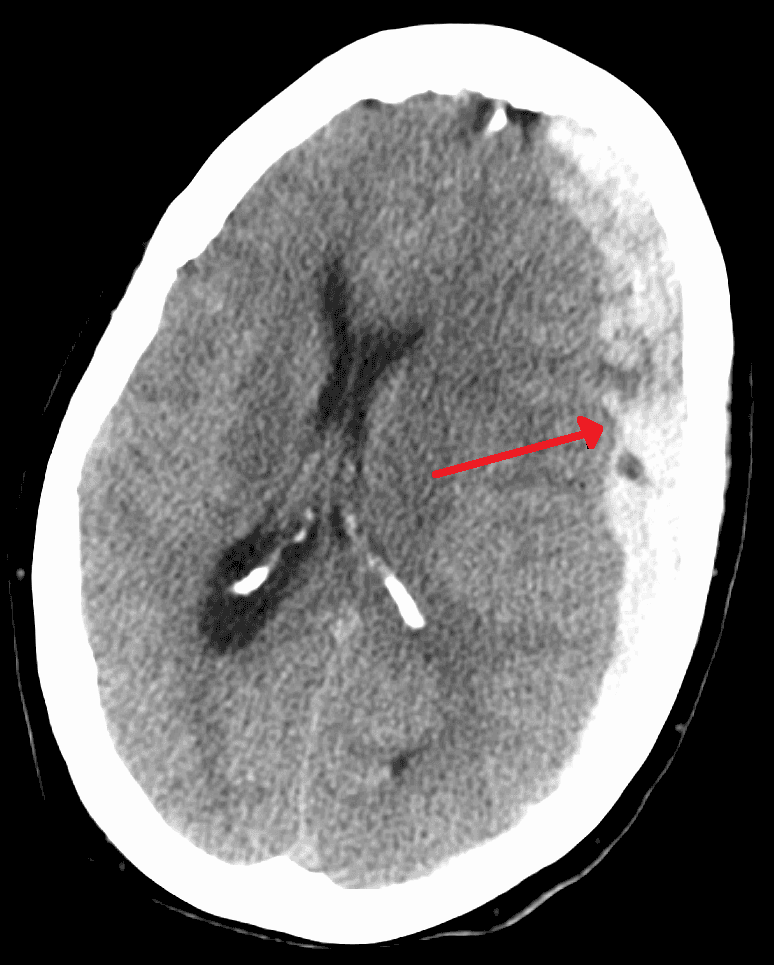

Le syndrome du bébé secoué (SBS) _ ou Traumatisme crânien infligé par secouement (TCIS) _ est un ensemble de signes cliniques concernant un nourrisson : hématome sous-dural,hémorragie rétinienne, œdème cérébral, ce que l'on appelle parfois la « triade ». Ils indiquent dans la plupart des cas que l'enfant a subi une violence physique, généralement que l'enfant a été secoué par un adulte. Plus précisément que la tête a été secouée en tenant le bébé par le tronc, ce mouvement de va-et-vient amplifiant le choc traumatique. Ceci pouvant être associé à un impact ou l'effet d'un impact sans secouement. Ce diagnostic clinique fait l'objet d'un consensus médical que l'on retrouve dans le diagnostics différentiels proposé par la HAS en 2017. Néanmoins, comme il sous entend une maltraitance grave, il est l'objet de controverses médico-légales visant à décorréler ce diagnostique médical d'un "diagnostique de maltraitance" en évoquant par exemple l'existence de maladies rares provoquant des symptômes similaires. L'enjeu étant que ce syndrome crée une très forte suspicion de maltraitance sur mineur qu'en France le soignant à l'obligation légale de signaler aux autorités afin qu'elles puissent procéder à une enquête, celle-ci pouvant aboutir dans certains cas à une qualification de crime et un jugement en cours d'assise. En France, le ministère de la santé rappel en 2022 que "Le syndrome du bébé secoué n’est généralement pas une violence isolée". Un bébé secoué l'à été en moyenne 10 fois. Le taux de récidive est de plus de 50 %. L'enfant décède dans 10 à 40 % des cas, 20% selon santé publique France en 2019. Et 75% des survivants conservent des séquelles graves à vie, dont souvent des « handicaps invisibles ». La cause du secouement est réputée être un adulte qui "craque" excédé par les pleurs de l'enfant, principe remis en cause par des mères de victimes. Dans les cas reconnus, 50% sont le fait du père, 20% d'un beau-père, 20% d'une personne extérieure, et 10% sont le fait de la mère.